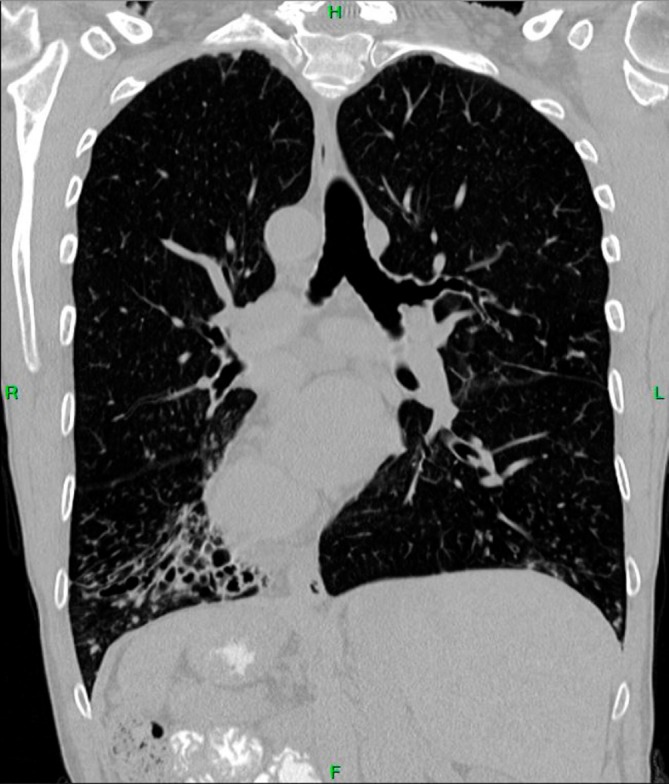

Kartagener综合征是一种罕见的常染色体隐性遗传病,以原发性纤毛运动障碍(PCD)为特征,导致纤毛粘膜清除和逆转部位受损。常见的症状是慢性复发性鼻窦炎、支气管扩张、中耳炎和肺炎。我们报告的情况下,62岁的女性患者完全倒置的胸部和腹部器官。支气管镜冲洗肺以获得治疗效果并培养靶向抗菌治疗。由于PCD引起的纤毛粘膜清除受损,卡塔赫纳综合征患者容易发生反复呼吸道感染和较低的BMI。通过肺部卫生进行多模式气道清除是一种有研究支持的治疗此病的策略。本病例强调了对有症状的Kartagener综合征和其他形式的原发性纤毛运动障碍(PCD)患者采取全面有效的治疗方法的重要性。

Kartagener's syndrome is a rare, autosomal recessive disorder characterised by primary ciliary dyskinesia (PCD) resulting in impaired mucociliary clearance and situs inversus. Common symptoms are chronic recurrent rhinosinusitis, bronchiectasis, otitis media and pneumonia. We report the case of a 62-year-old female patient with complete situs inversus of the chest and abdominal organs. Bronchoscopic washout of the lungs was performed for therapeutic benefit and culturing for targeted antibacterial therapy. Patients affected by Kartagener's syndrome are vulnerable to repeated respiratory infections and lower BMI due to impaired mucociliary clearance from PCD. Multimodal airway clearance through pulmonary hygiene is a research-backed strategy in treating this condition. This case highlights the importance of a comprehensive and effective management approach for patients with symptomatic Kartagener's syndrome and other forms of primary ciliary dyskinesia (PCD).